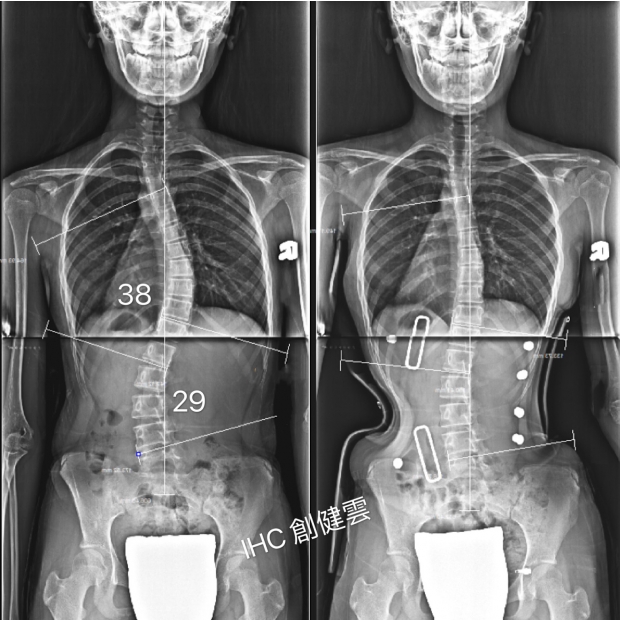

13歲脊椎側彎女孩

側彎38度